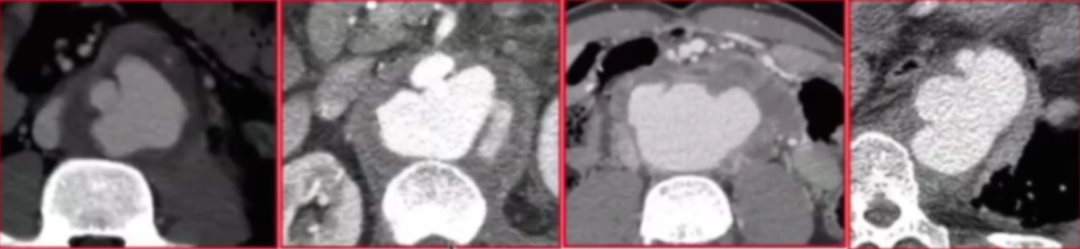

该研究(2005年9月-2024年5月)共纳入175例感染性主动脉瘤患者(男性142,女性33例),平均年龄64.8岁。这些患者患病部位为胸主动脉31例、内脏分支受累26例、胸腹联合5例、腹主动脉113例。

临床表现主动脉周围炎症97%、瘤体渗漏76%,部分患者合并椎体侵蚀、腔静脉血栓。

长期预后&动脉瘤瘤囊变化

针对156例出院患者进行长期随访,平均随访时间为47个月(随访时长范围1-201个月),主要关注动脉瘤瘤囊变化和疾病复发情况。在156例长期随访的患者中,86%的患者瘤囊变化呈现有利态势,其中56%为瘤囊显著缩小(缩小幅度≥5cm),30%实现瘤囊完全消退;仅5%的患者瘤囊出现增大,9%的患者瘤囊保持稳定。这说明感染性主动脉瘤经腔内治疗后,长期来看多数患者的瘤囊能够得到良好控制。

不过研究也客观呈现了治疗失败的情况,总失败率为11.5%,主要分为两类:一类是手术相关(技术)失败,占比7.7%,多因近远端密封不足导致。

案例5:患者采用双肾烟囱技术EVAR的患者因近端覆盖不足,后续通过“近端补片延伸+烟囱技术+延伸型三分支腹主动脉腔内修复术(Extended3-branchChimneysEVAR)”等方式处理,术后6年半随访显示动脉瘤完全缩小,取得良好效果。